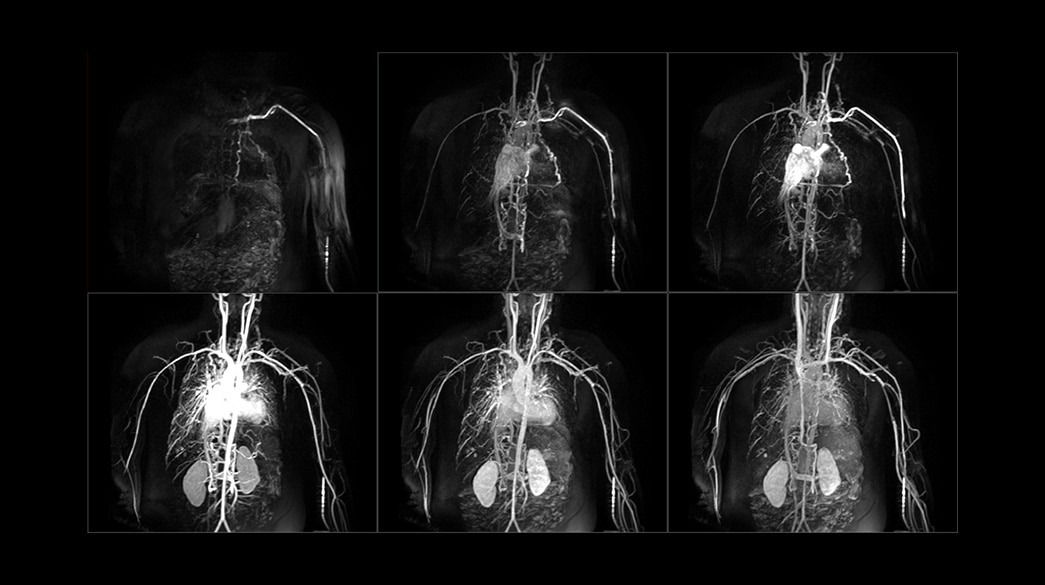

<p>Fluoro Trigger MRA</p>

Read case study ico-caret-right

<p>TRICKS</p>

<p>Inhance Suite</p>

Learn more ico-caret-right